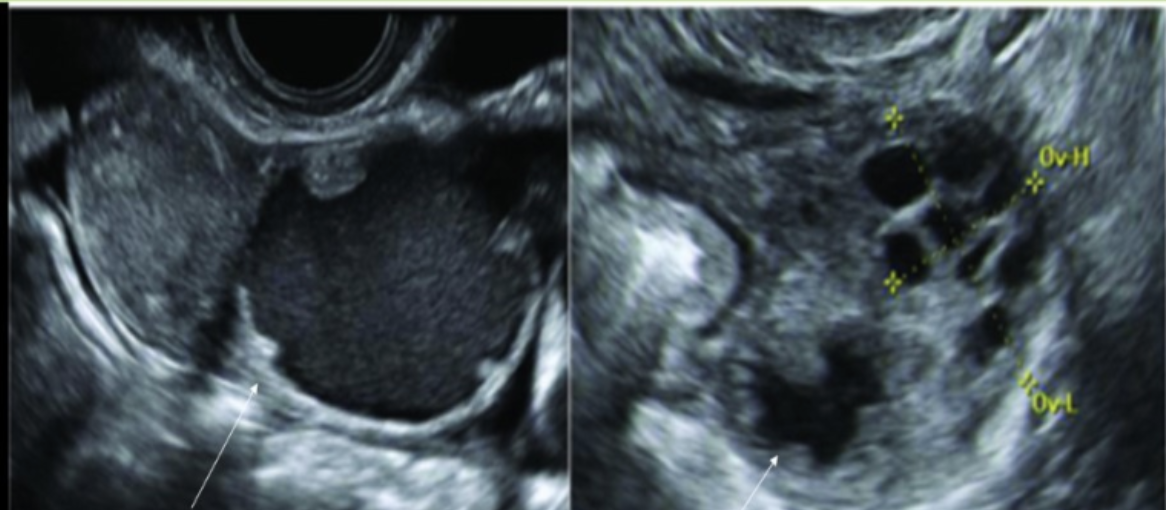

pt has amenorrhea + hirsutism. if the right ovary has the same appearance,

a) normal ovary w/multiple follicles

b) partial ovarian torsion

c) ovarian hyperstimulation

d) possible stein-leventhal syndrome

26 yo w/pelvic pain + discharge for 3 weeks, LMP 3.5 weeks ago, G1, P2. lab shows leukocytosis

a) dilated pelvic veins next to ovary, can be complication for mothers of multiple births

b) dilated fallopian tube w/internal debris + nodularity consistent w/carcinoma formation

c) dilated, anechoic fallopian tube medial to the ovary, aka hydrosalpinx, consistent w/probable PID

d) dilated fallopian tube due to the presence of interstitial ectopic pregnancy